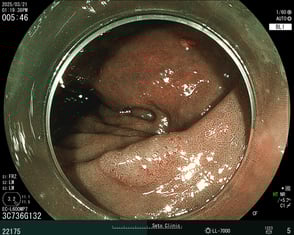

通常光でポリープを発見

強調画像で詳細に観察して治療することに決定